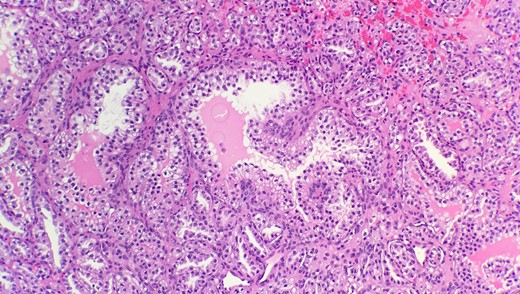

Pathological diagnosis confirmed CCPRCC. Grossly, the partial nephrectomy specimen measured 4 × 3.1 × 2.2 cm. The attached fatty tissue surrounding the kidney measured 10.5 × 7.8 × 2.5 cm. Cut sections showed a tan pink nodule with foci of white tan tissue measuring 3.5 cm. Microscopic examination reveals that the tumor is composed of cystic, tubular, solid and papillary components with clear cells and a low nuclear grade (Fig. 1). Tumor cells were also positive for CK7 (Fig. 2) and negative for CD10 (Fig. 3) and p504s supporting the diagnosis of CCPRCC.

Immunohistochemical stain reveals that tumor cells are positive for CK7 (IHC 40x).